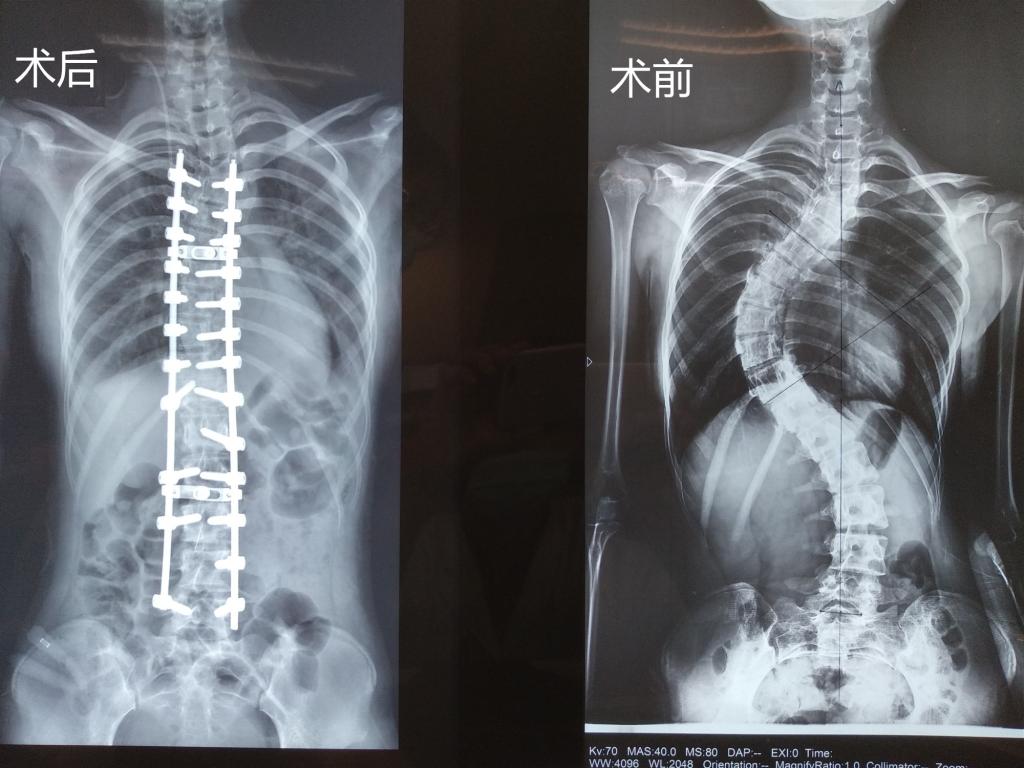

據(jù)我院脊柱骨科主任胡朝暉介紹,小孔來院檢查時脊柱側(cè)凸畸形非常嚴(yán)重,已經(jīng)對女孩的日常生活造成了嚴(yán)重影響,且畸形極可能進(jìn)一步加重,壓迫心臟、肺、腹部等臟器,引起呼吸困難等心肺腹問題,還可能會出現(xiàn)頑固性背痛、站立和行走困難、跛行、肢體無力、大小便失禁等癥狀,必須通過手術(shù)對其脊柱側(cè)凸畸形進(jìn)行矯形、固定。

“患者椎骨結(jié)構(gòu)異常,椎體旋轉(zhuǎn),椎弓根細(xì)小,均會導(dǎo)致術(shù)中置釘難度大大增加,且患者患者肺功能已受限,手術(shù)矯形后,兩肺空間重新分布,兩側(cè)胸腔大量積液會加重呼吸困難、甚至危及生命……”面對這一系列的困難,脊柱骨科醫(yī)療團(tuán)隊為小孔設(shè)計了多套應(yīng)急預(yù)案,做好充分準(zhǔn)備來應(yīng)對可能出現(xiàn)的所有情況,確保手術(shù)萬無一失。

幾天后,脊柱骨科醫(yī)療團(tuán)隊頂著巨大的精神壓力為小孔進(jìn)行脊柱側(cè)彎矯正術(shù),術(shù)中置入26枚螺釘,歷時近7小時,手術(shù)非常成功,麻醉清醒后,小孔的雙腿可以自如活動,此刻包括胡朝暉主任在內(nèi)的所有醫(yī)護(hù)人員都打心眼里為她高興。

術(shù)后恢復(fù)期,護(hù)理團(tuán)隊密切配合,精心呵護(hù),小孔的狀態(tài)一天比一天好,當(dāng)她第一次下地活動,驚喜地發(fā)現(xiàn)自背竟然挺起來了!醫(yī)務(wù)人員告訴她,她足足長高了6公分!小孔激動得眼淚都要掉下來了:我的生活終于回歸正常,感謝各位叔叔阿姨!